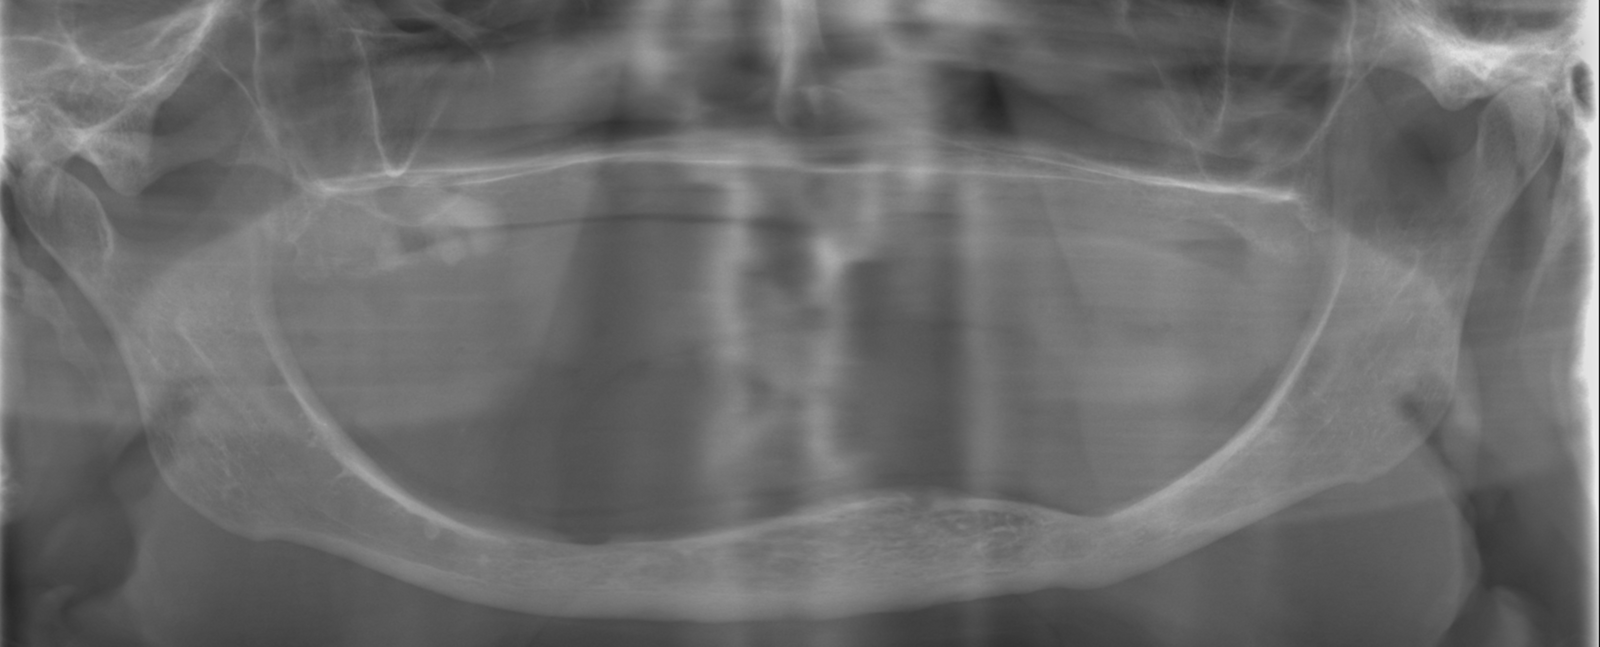

Een 80-jarige patiënte, bekend met gebruik van bloedverdunners, presenteerde zich met functionele en esthetische klachten door volledig uitneembare prothesen in boven- en onderkaak die zij al >40 jaar droeg. De prothesetanden waren sterk versleten en zowel retentie als stabiliteit was matig, wat leidde tot kauwproblemen en verminderd comfort. Klinisch en radiologisch werd een zeer ernstige resorptie vastgesteld in zowel de maxilla als de mandibula, passend bij Cawood & Howell-classificatie V–VI (figuur 9-11).

Preoperatieve situatie op een OPT.

CBCT-scan preoperatief.